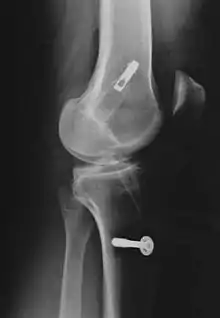

Le décollement ou l'arrachement du LCA de l'os est substantiellement plus rare que la rupture intraligamentaire[5] et n'est pas une rupture de ligament. Ce cas particulier survient plus fréquemment chez les enfants, particulièrement dans le domaine du tubercule intercondylaire du tibia, et possède en général, par refixation de l'arrachement par exemple avec des vis ou des fils métalliques, de bonnes chances de guérison complète.

Les radios n'apportent aucune contribution immédiate au diagnostic de rupture de LC. Les deux LC sont invisibles à la radio, déchirés ou non. La seule utilité de la radio ne peut servir qu'au diagnostic des complications osseuses possibles.